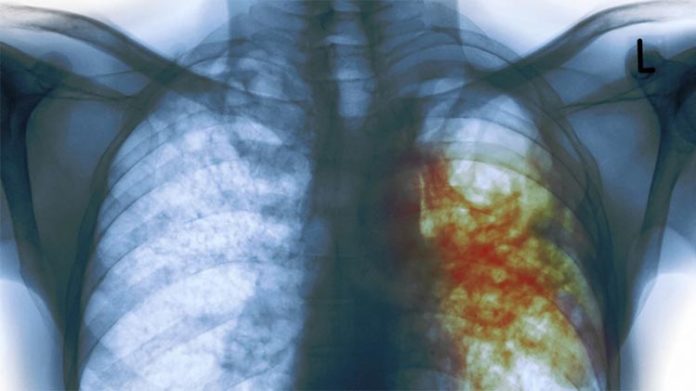

Más de diez millones de personas en el mundo enfermaron de tuberculosis en todo el mundo en 2016. Las cifras de prevalencia de la lepra son bastante menores, ya que unos 10.000 casos son detectados cada año, el 96% en países en vías de desarrollo.